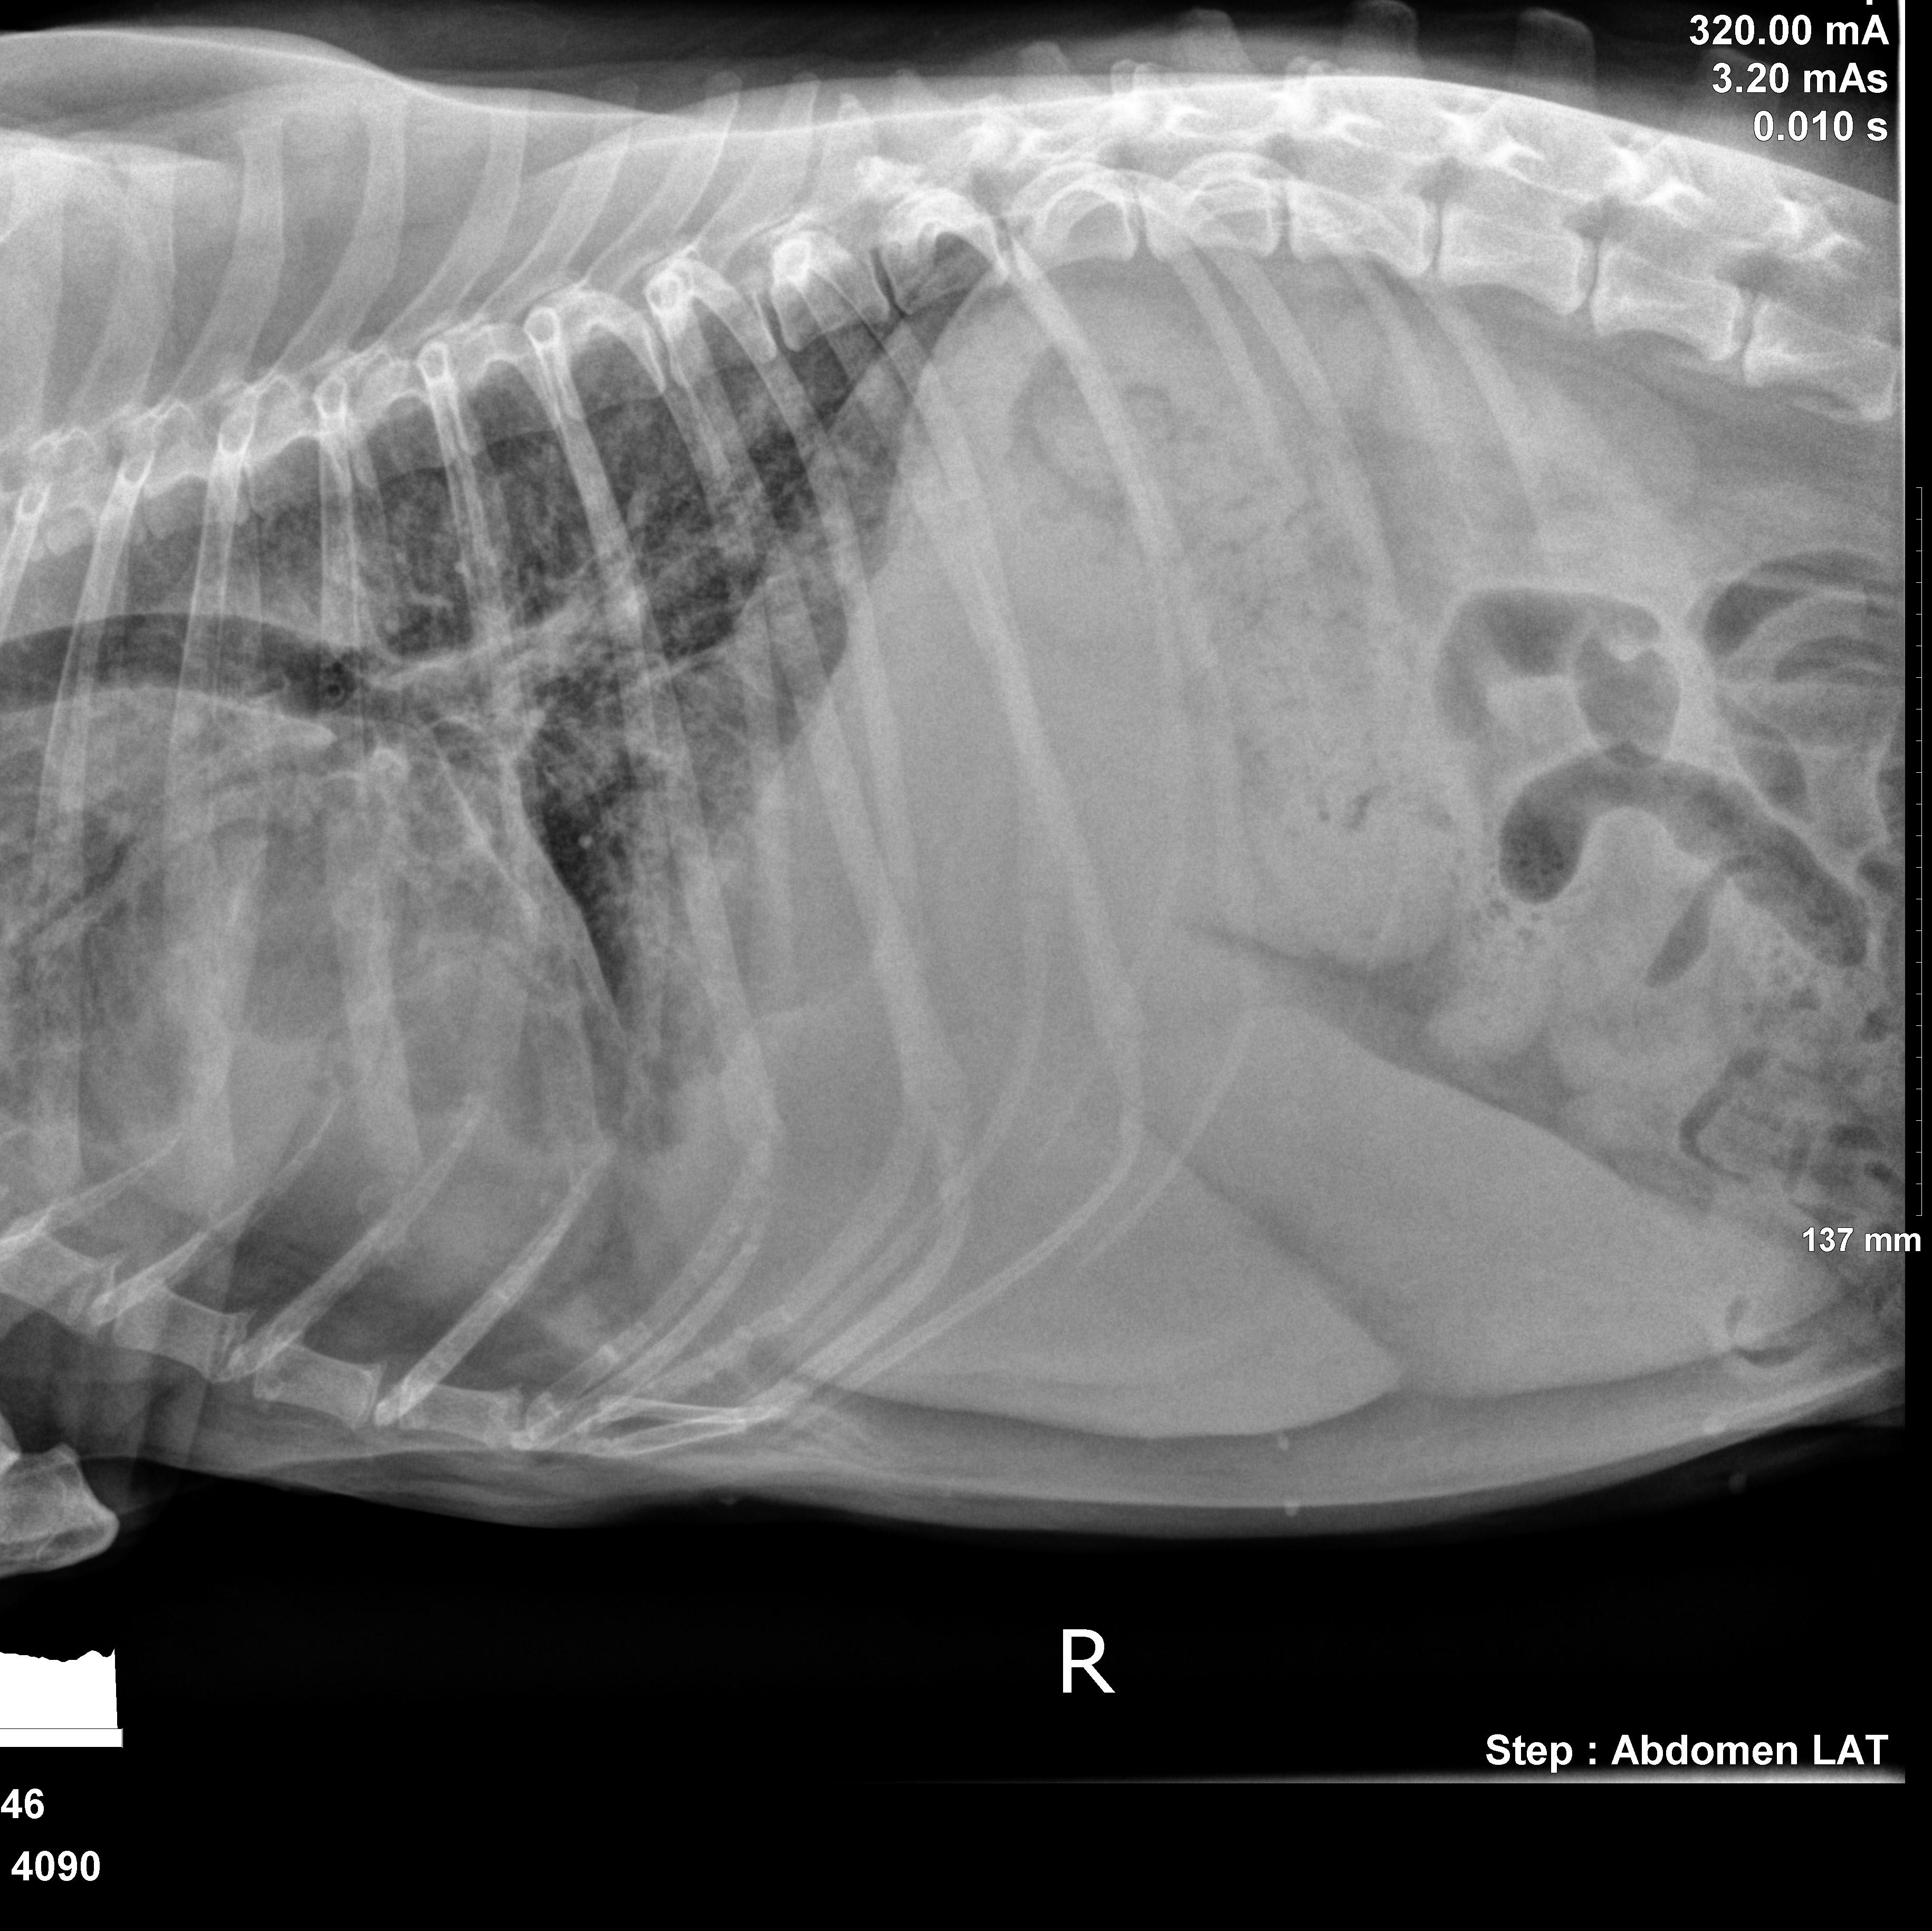

My dog (11 year old Golden Retriever) was very lethargic, not eating, breathing heavy, and weak on her legs about a month ago. I took her in to 24 hour vet and they did x-rays and blood work. Her platelets were at 7. Based on x-rays, the vet concluded that she has a spleen tumor and put her on prednisone. The vet gave her 5 to 6 months. I haven't take her in to regular vet because they are always booked week in advance. Just wanted to get second opinion based on photos provided. Thanks.

It can be very difficult to evaluate x-rays without being on the computer that took them - I can't manipulate the lightness and darkness or zoom in all the way. That being said, I am concerned that there is something very serious going on in Jasmine's liver. It is much, much larger than in a normal dog. I can't see the entire spleen, but the parts that I see appear normal. I can also see that there is some free fluid in her chest cavity - this would be fluid between the lungs and chest wall that can cause trouble breathing. I would recommend re-evaluation immediately with an emergency vet. There could be many things going on, but the heavy breathing you described combined with the abnormalities in the chest have me worried that she may be having severe issues with breathing. This can cause severe anxiety and stress in a dog. The vet will probably want to repeat the x-rays and bloodwork, and may be able to draw off fluid if it is still there to ease her breathing.